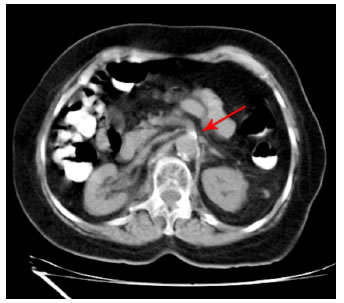

Fue hospitalizada en el servicio de geriatría; en la tomografía computarizada (TC) con contraste de abdomen se observó esteatosis hepática difusa, enfermedad arterioesclerótica aórtica grave y diverticulosis leve no complicada en el colon (figura 1). En el aortograma se documentó estenosis del 70 % de la arteria mesentérica superior y de la arteria renal derecha, del 30 % del tronco celiaco, del 40 % de la arteria mesentérica superior y del 90 % de la arteria iliaca común izquierda (figura 2).